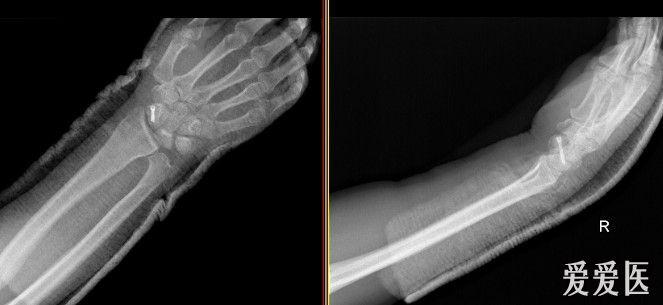

腕の骨折 脱臼時のギプスの固定に。ニューアームサスペンダー 品番: 適用範囲(裄丈):65~90cm 対応身長145~185cm 左右兼用 腕の骨折 脱臼時のギプスの固定に、首が凝らない腕つりサポーター。ファーストレイト アームスリング 品番:JAS1橈骨遠位端骨折(とうこつえんいたんこっせつ) 橈骨遠位端骨折は、ころんで手をついた際におこる骨折で、頻度の高い疾患です。 特に骨粗鬆症のある方では多発します。 手のつき方、骨折線の入り方によって、様々な骨折のタイプがあります。

右手骨折 手術- 橈骨遠位端骨折は骨折の中でも、比較的多く見られる骨折です。 しかし、「橈骨遠位端骨折とうこつえんいたんこっせつ」と聞いてもピンとこない方がほとんどだと思います。 では、橈骨とはどこの骨で、どんな骨折なのでしょうか? 上の骨折部位 1.中手骨骨幹部 (こっかんぶ) 骨折 原因: 中手骨の中央部を骨幹部といい、この部での骨折です。 物が手の甲に当たるなど、強い力が直接骨に加わったり、手をひねる力が加わったりして発生します(図2、3)。 症状:

手首の骨折の治療法 手首の骨折の治療は、自然治癒力によって癒合させるのが基本です。 応急処置 応急処置は症状の悪化を防ぎます。骨折部がズレると治療行程が増えて、治療期間が長引きます。 まずは副木で手首の関節を固定します。 良いほうの右手の骨と比べて見ても、 ほぼ変わりないくらい骨折部分がきれいに治っていることがわかります。 この時点で、しっかり治ったことを確認して、 通院終了となりました。骨折部位によって骨の転位方向が変わります。 a, 基部:浅指屈筋腱付着部よりも 近位 で折れた場合は 屈曲変形(背側凸) が起こりやすく(図41) b, 中央:浅指屈筋腱付着部よりも 遠位 で折れた場合は 伸展変形(掌側凸) の変形になりやすい(図42) c, 遠位:受傷機転により変形方向が